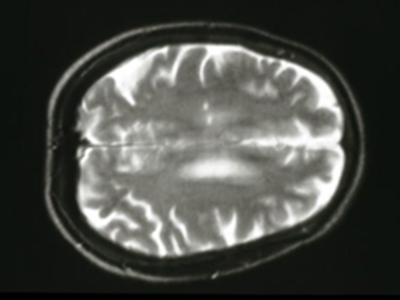

Почти два миллиона человек во всем мире страдают от рассеянного склероза - аутоиммунного заболевания, поражающего нервные волокна головного и спинного мозга. В наиболее тяжелых случаях болезнь может привести к преждевременной смерти. Ученые из Университета Британской Колумбии обнаружили миссенс-мутацию в гене NR1H3, пишет The Times of India.

Миссенс-мутация - изменение в нуклеотидной последовательности ДНК, вызывающее замену в белке одной аминокислоты на другую. В данном случае мутация нарушала работу белка LXRA. Он контролирует воспаление, врожденный иммунитет и липидный обмен. Все эти факторы тесно связаны с рассеянным склерозом.

У носителей мутации риск развития этого заболевания оказался повышен на 70%. Кроме того, они были склонны к агрессивной форме рассеянного склероза. Также у мышей с миссенс-мутацией в NR1H3 отмечались неврологические нарушения. В частности, у них вырабатывалось меньше миелина (вещества, образующего защитную оболочку нервных волокон). Носителями мутации оказались две трети членов двух семей из Канады, участвовавших в исследовании.